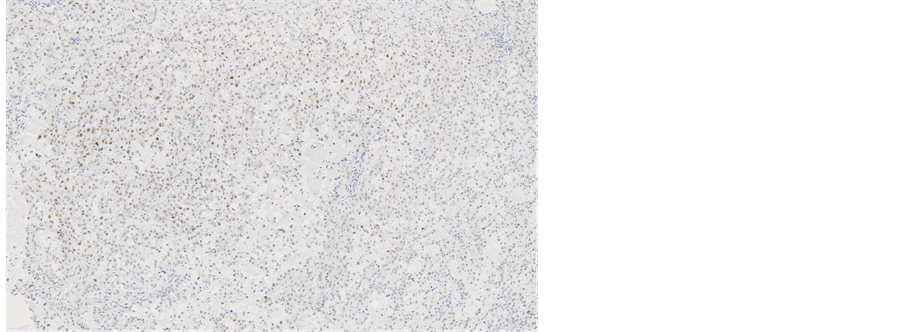

Immunohistochemical staining showed, that the tumour cells were diffusely positive for monoclonal antibodies against pancytokeratin (AE1/AE3) (Figure 5), cytokeratin 7 was positive in 5% of tumour cells (Figure 6), other markers, which showed immunoreactivity: EMA (5%), RCC-smp314 (30%), CA-125 (30%), p53 (was expressed weakly) (Figure 7), AMACR (diffuse positivity), CD10 (50%), Cyclin D1 (40% - 50%) and bcl-2. The tumour cells were negative for Vimentin (Figure 8), WT1 (Figure 9), Cytokeratin 20, ER/PR, CEA (Figure 10), TTF-1, CD57.

Figure 7. Microscopic appearance of the endometrial tissue from curetting specimen-clear cell carcinoma, immunohistochemical staining with monoclonal antibodies against p53, ×10.